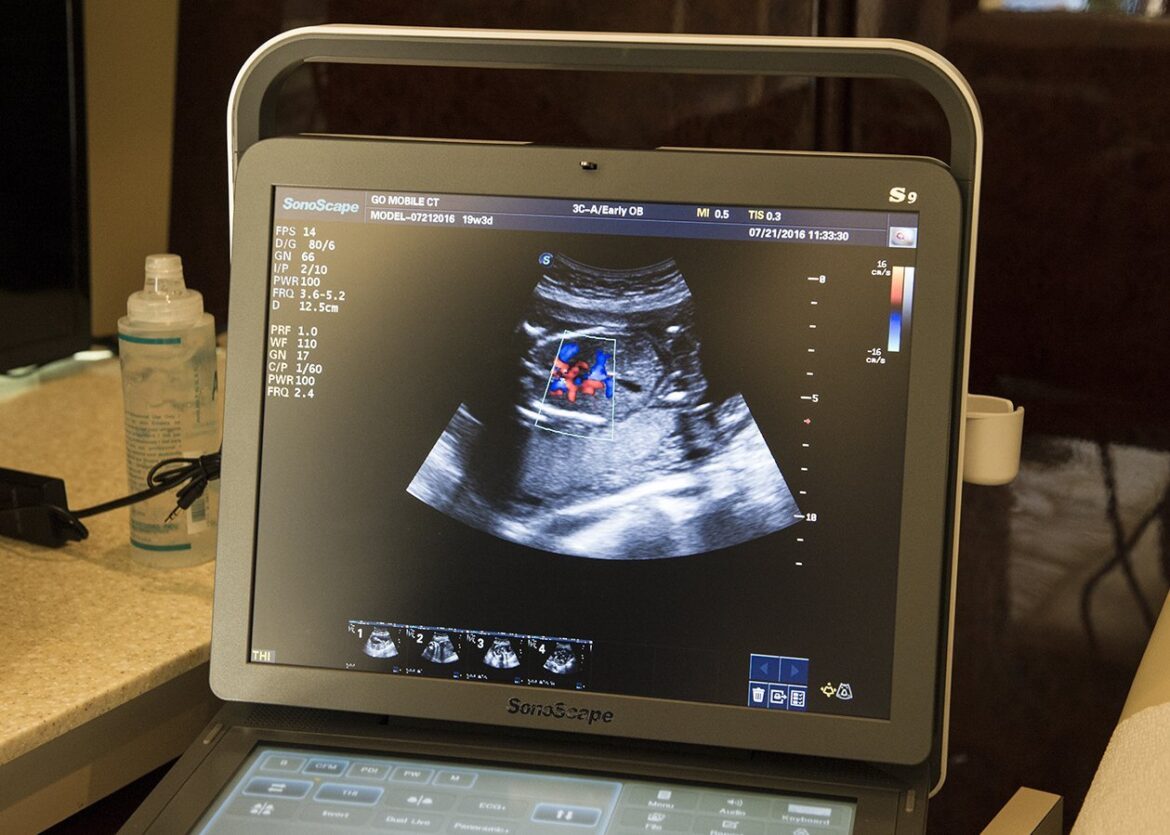

(OSV News) — Idaho lawmakers recently approved legislation that will require public schools to teach fetal development and show ultrasound video to students in grades five to 12.

Republican Gov. Brad Little on March 27 signed Senate Bill 1046 into law, requiring schools that teach subjects such as human biology or health classes including information about sexually transmitted diseases show a “high-definition ultrasound video” that is at least three minutes long “showing the development of the brain, heart, sex organs, and other vital organs in early fetal development.”

Or, the bill says, schools must show an equivalent “high-quality, computer-generated rendering or animation showing the process of fertilization and every stage of human development inside the uterus, noting significant markers in cell growth and organ development for every week of pregnancy until birth.”